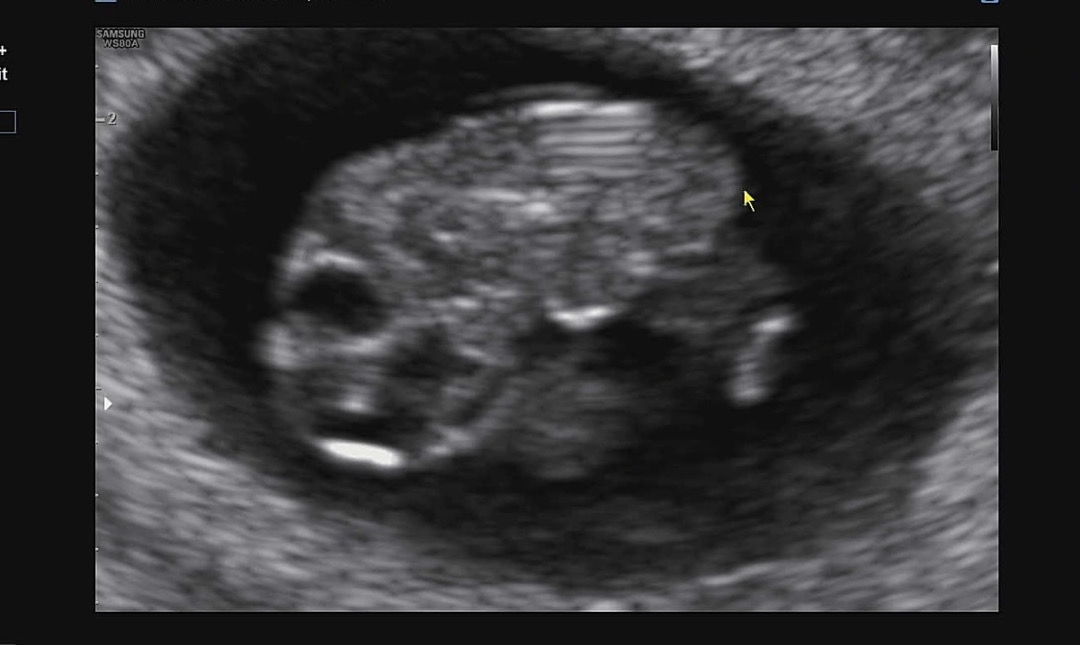

8주2일 아기!

1.98cm에 심장박동 179bpm이면 적당한거죠? 한 9일 사이에 0.85cm에서 1.98cm로 왕창 커졌더라구요 ㅎㅎ 초음파 안보는 동안 너무 불안했는데 생각보다 잘 크고있어서 신기했네요🤭 아쉽게도 젤리곰은 못보고 옆모습만 보고왔어요 ㅎㅎ